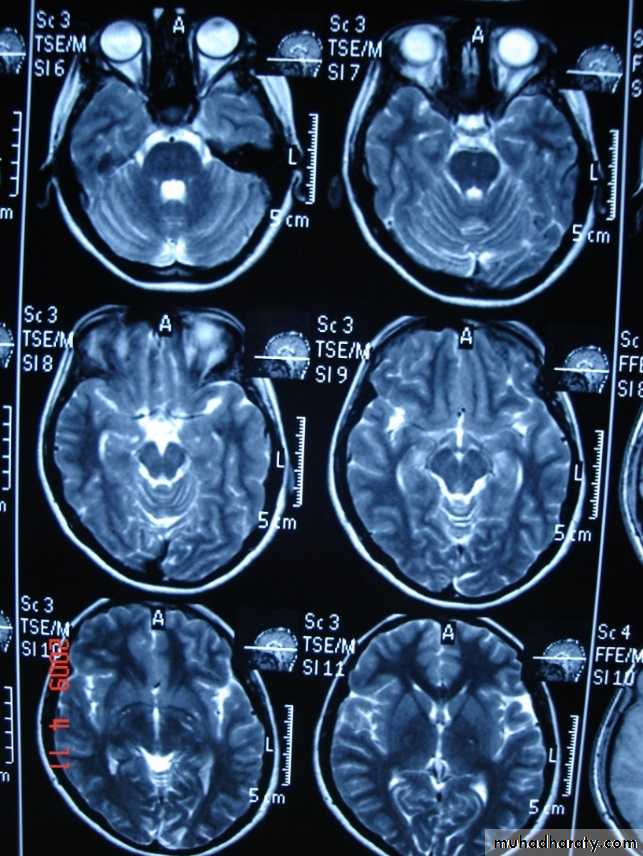

MRI

T1 T2

T 2/ FLAIR SEQUENCE: fluid attenuation inversion recoveryT 1w + GADOLINEUM INJECTION / SAGITAL SECTION